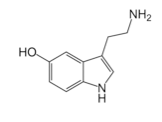

• Triptofan, 5-htp, Szerotonin

• Antidepresszánsok és az 5-HTP

• Kolin, szerotonin az agyműködés és a memória segítője